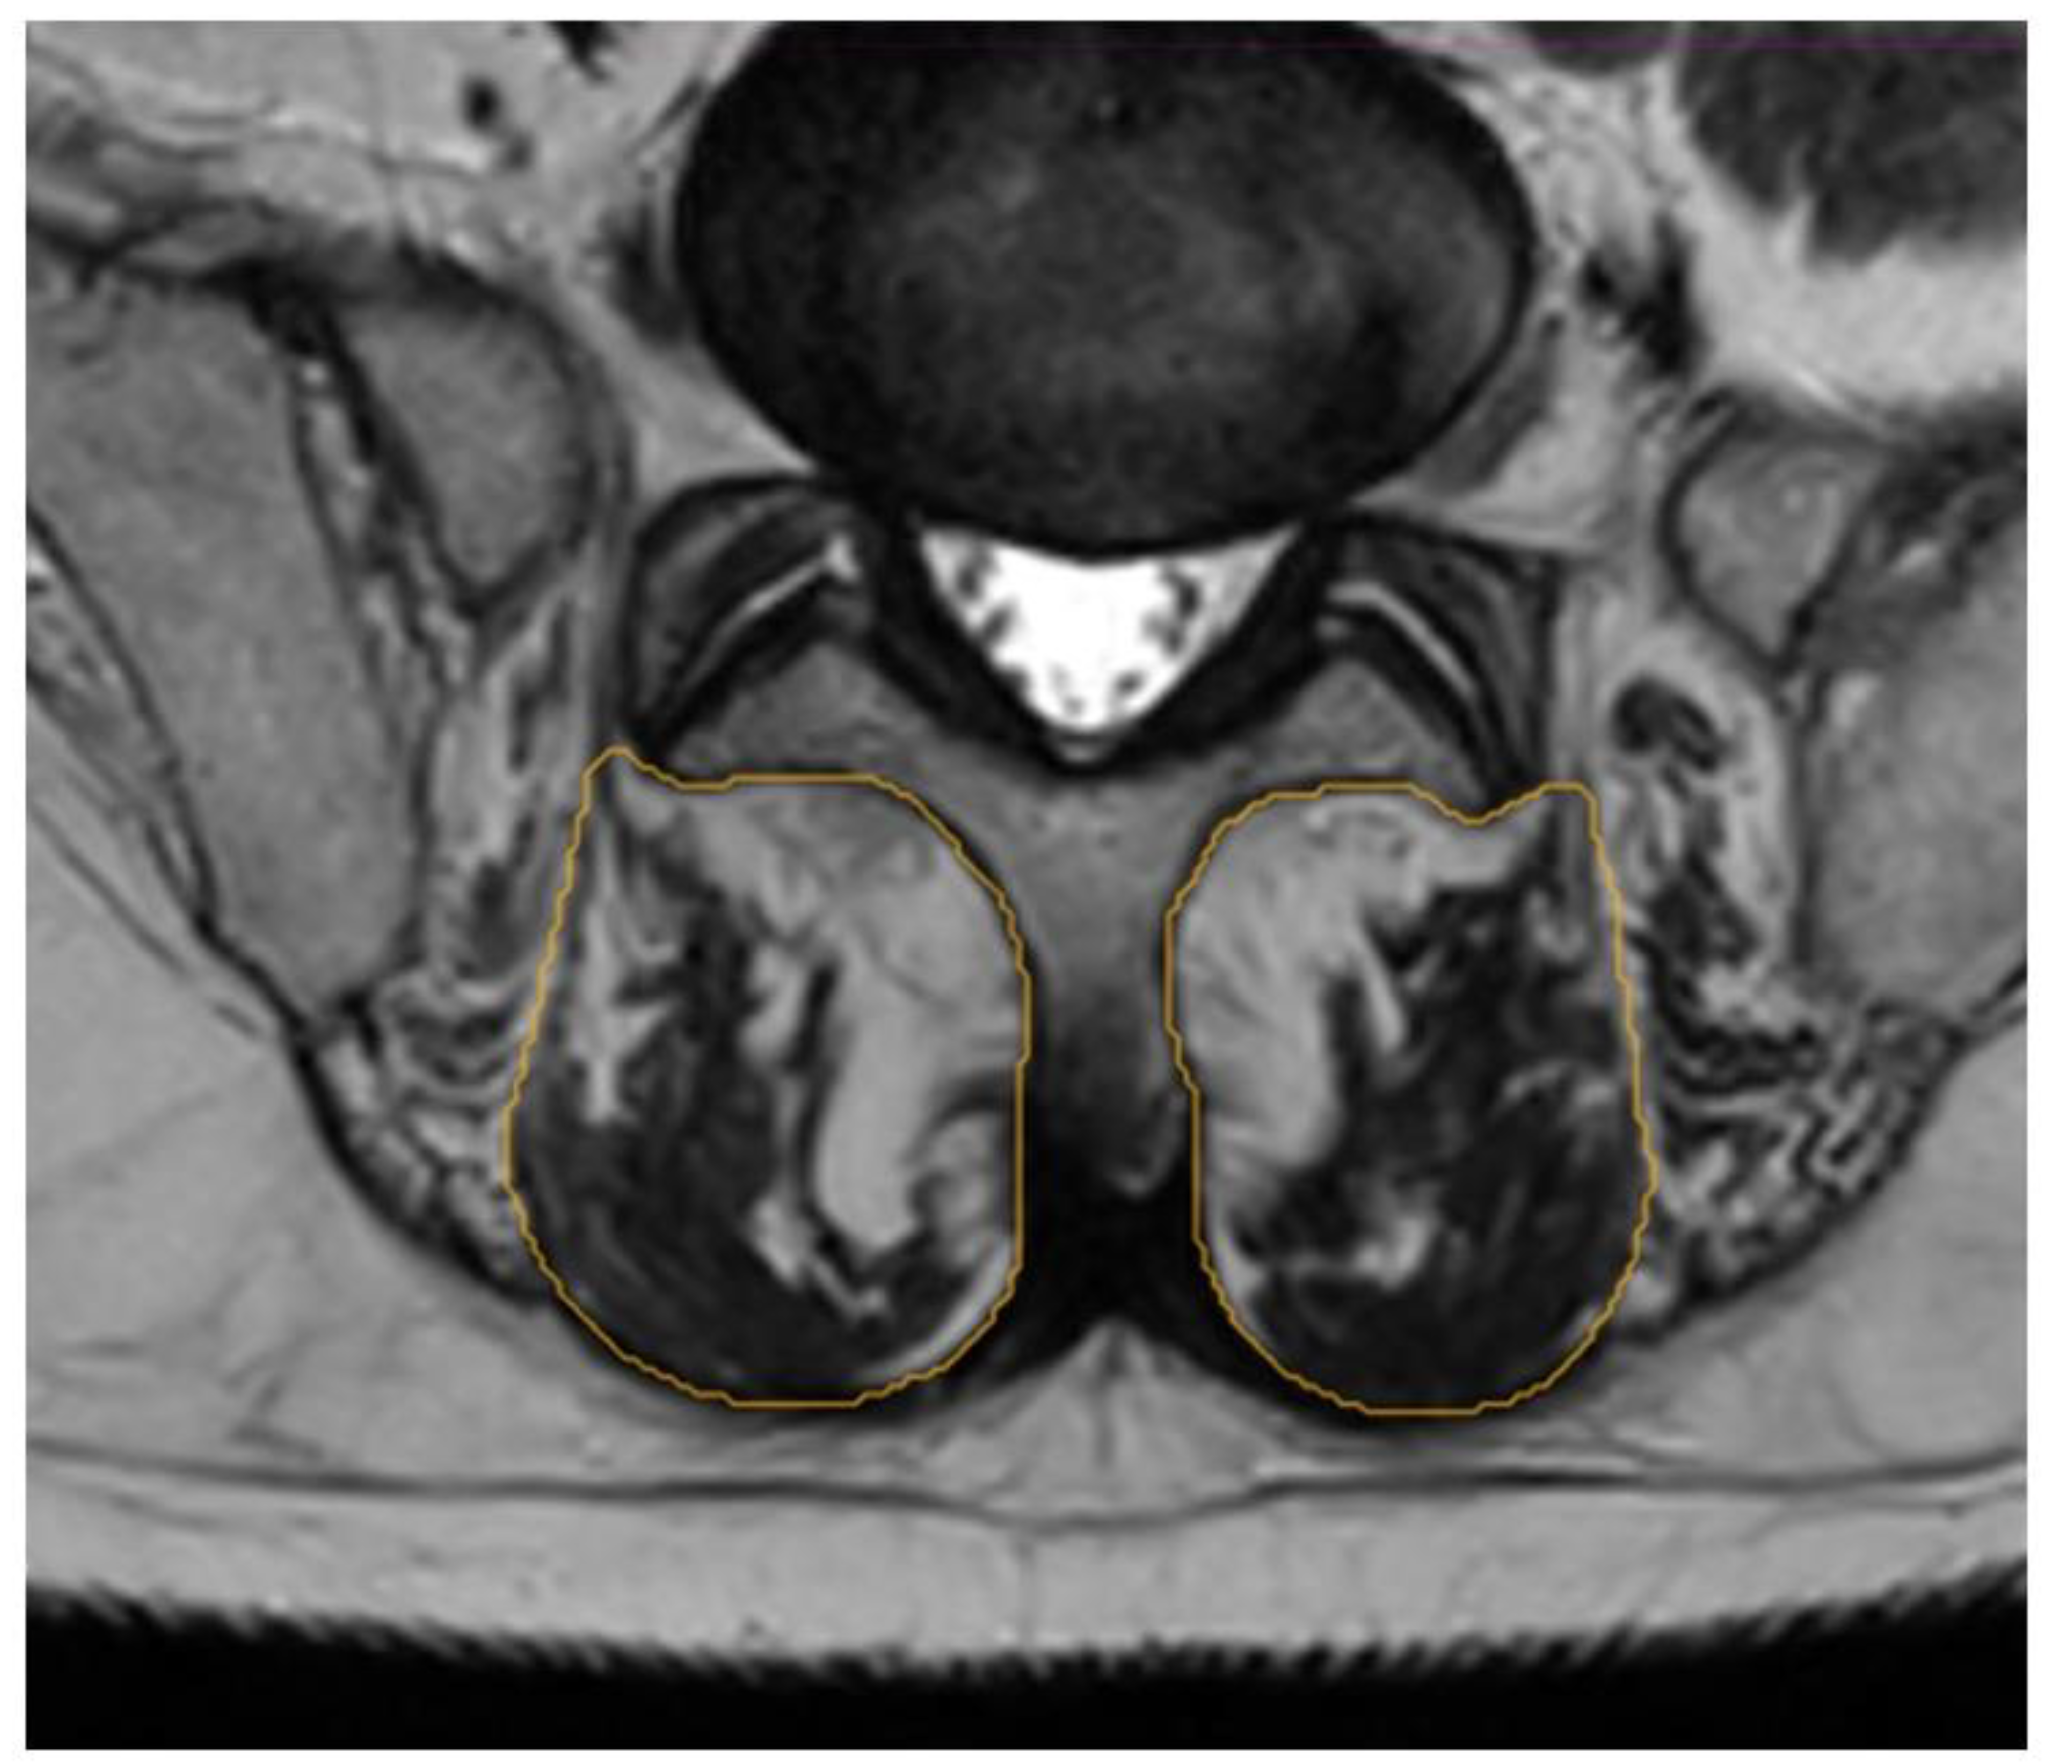

2.3. Segmentation Composition Analysis

3.3. Reliability Analysis